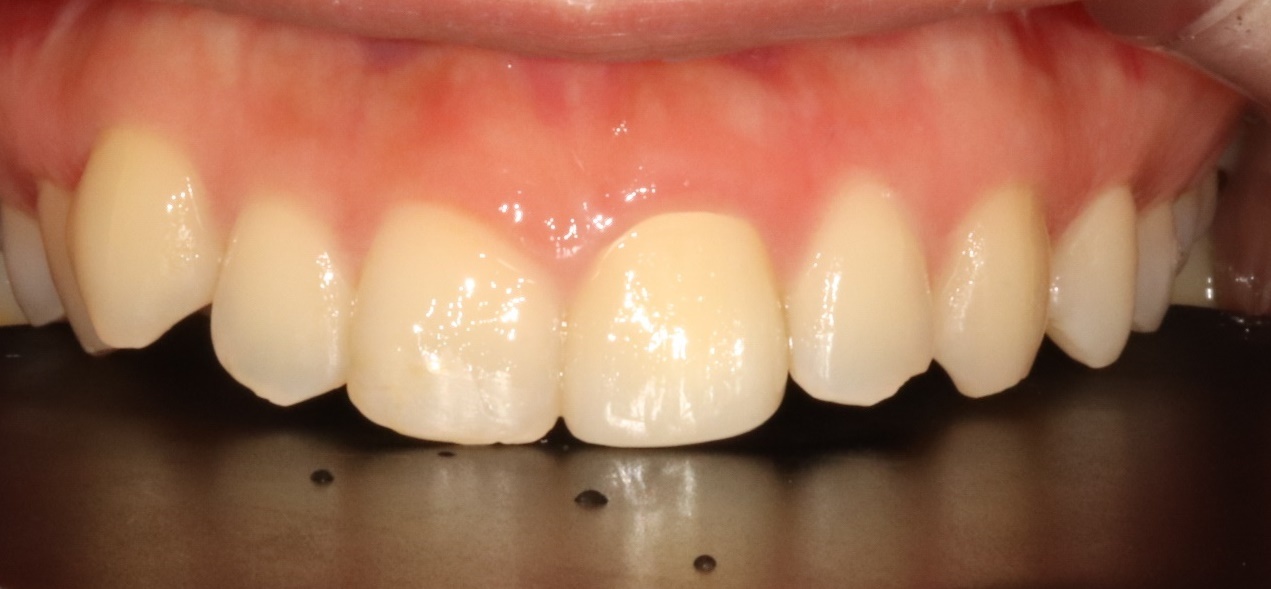

앞니 크라운

Before

After

외상으로 파절된 앞니를 자연스럽게 복원